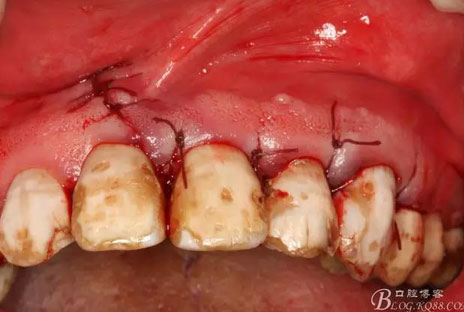

圖4.囊腫術(shù)前的口內(nèi)檢查:21、22牙冠未變色、唇側(cè)粘膜色澤正常,無瘺管,可在前庭溝捫及隆起,有乒乓感。

圖7.11近中的垂直切口

圖10.翻開粘膜瓣發(fā)現(xiàn)有唇側(cè)部分骨壁不規(guī)則缺損。

圖11.逐漸去骨薄如蟬翼的骨壁,暴露出完整的囊壁

圖12.暴露出的完整囊壁,真夠大!

圖19.縫合